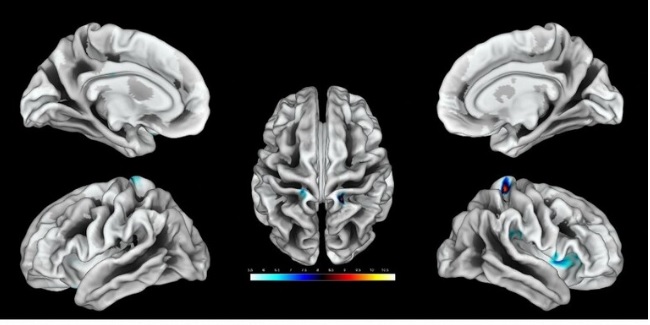

وبحثت الدراسة مرحلة إزالة أو نزع الاستقطاب في القشرة الدماغية البشرية وقدمت فهما أفضل لكيفية استجابة الدماغ لنفاد الطاقة، حيث قدمت لأول مرة فهما كاملا حول الفيزيولوجيا الكهربية للموت الذي يحدث عقب توقف الدورة الدموية في الدماغ البشري.

وأشار المقال إلى وجود دراستين جديدتين ستنشران في مجلة "Brain" العلمية، قام بهما فريق من العلماء كجزء من دراسة كبيرة تركز على مرحلة إزالة الاستقطاب في الدماغ، حيث وصف العلماء لأول مرة مرحلة "الموجة الكهربائية" للموت الدماغي.

وقال درير إن انتشار عمليات إزالة الاستقطاب أو "تسونامي الدماغ"، تعتبر بجميع المقاييس من أكبر الأحداث التي تصيب الدماغ الحي، وهي أشد من نوبات الصرع وتتعلق بالتغيرات الأيونية وتغيرات الناقل العصبي والتغيرات الكهربية والعديد من الجوانب الفيزيولوجية المرضية الأخرى التي تصيب الدماغ، وترتبط بتدفق كمية هائلة من الماء إلى الخلايا العصبية، مما يؤدي إلى تضخمها.

إلى ذلك، ذكرت الدراسة أن "هذه الموجة المنتشرة القابلة للعكس والتي يمكن عكسها تبدأ عادة بعد 2 إلى 5 دقائق من ظهور نقص التروية الحاد، مما يشير إلى بداية تغير عصبي سام يؤدي في النهاية إلى إصابة لا رجعة فيها".

وأجرى العلماء تسجيلات من خلال تركيب شرائط أو صفائف قطب كهربائي لدى المرضى الذين تعرضوا لتلف دماغي حاد أدى إلى دخولهم في حالة لا رجعة منها أو ميؤوس منها تستوجب فقط بعض العلاجات التخفيفية بدون وجود فرصة للإنعاش.